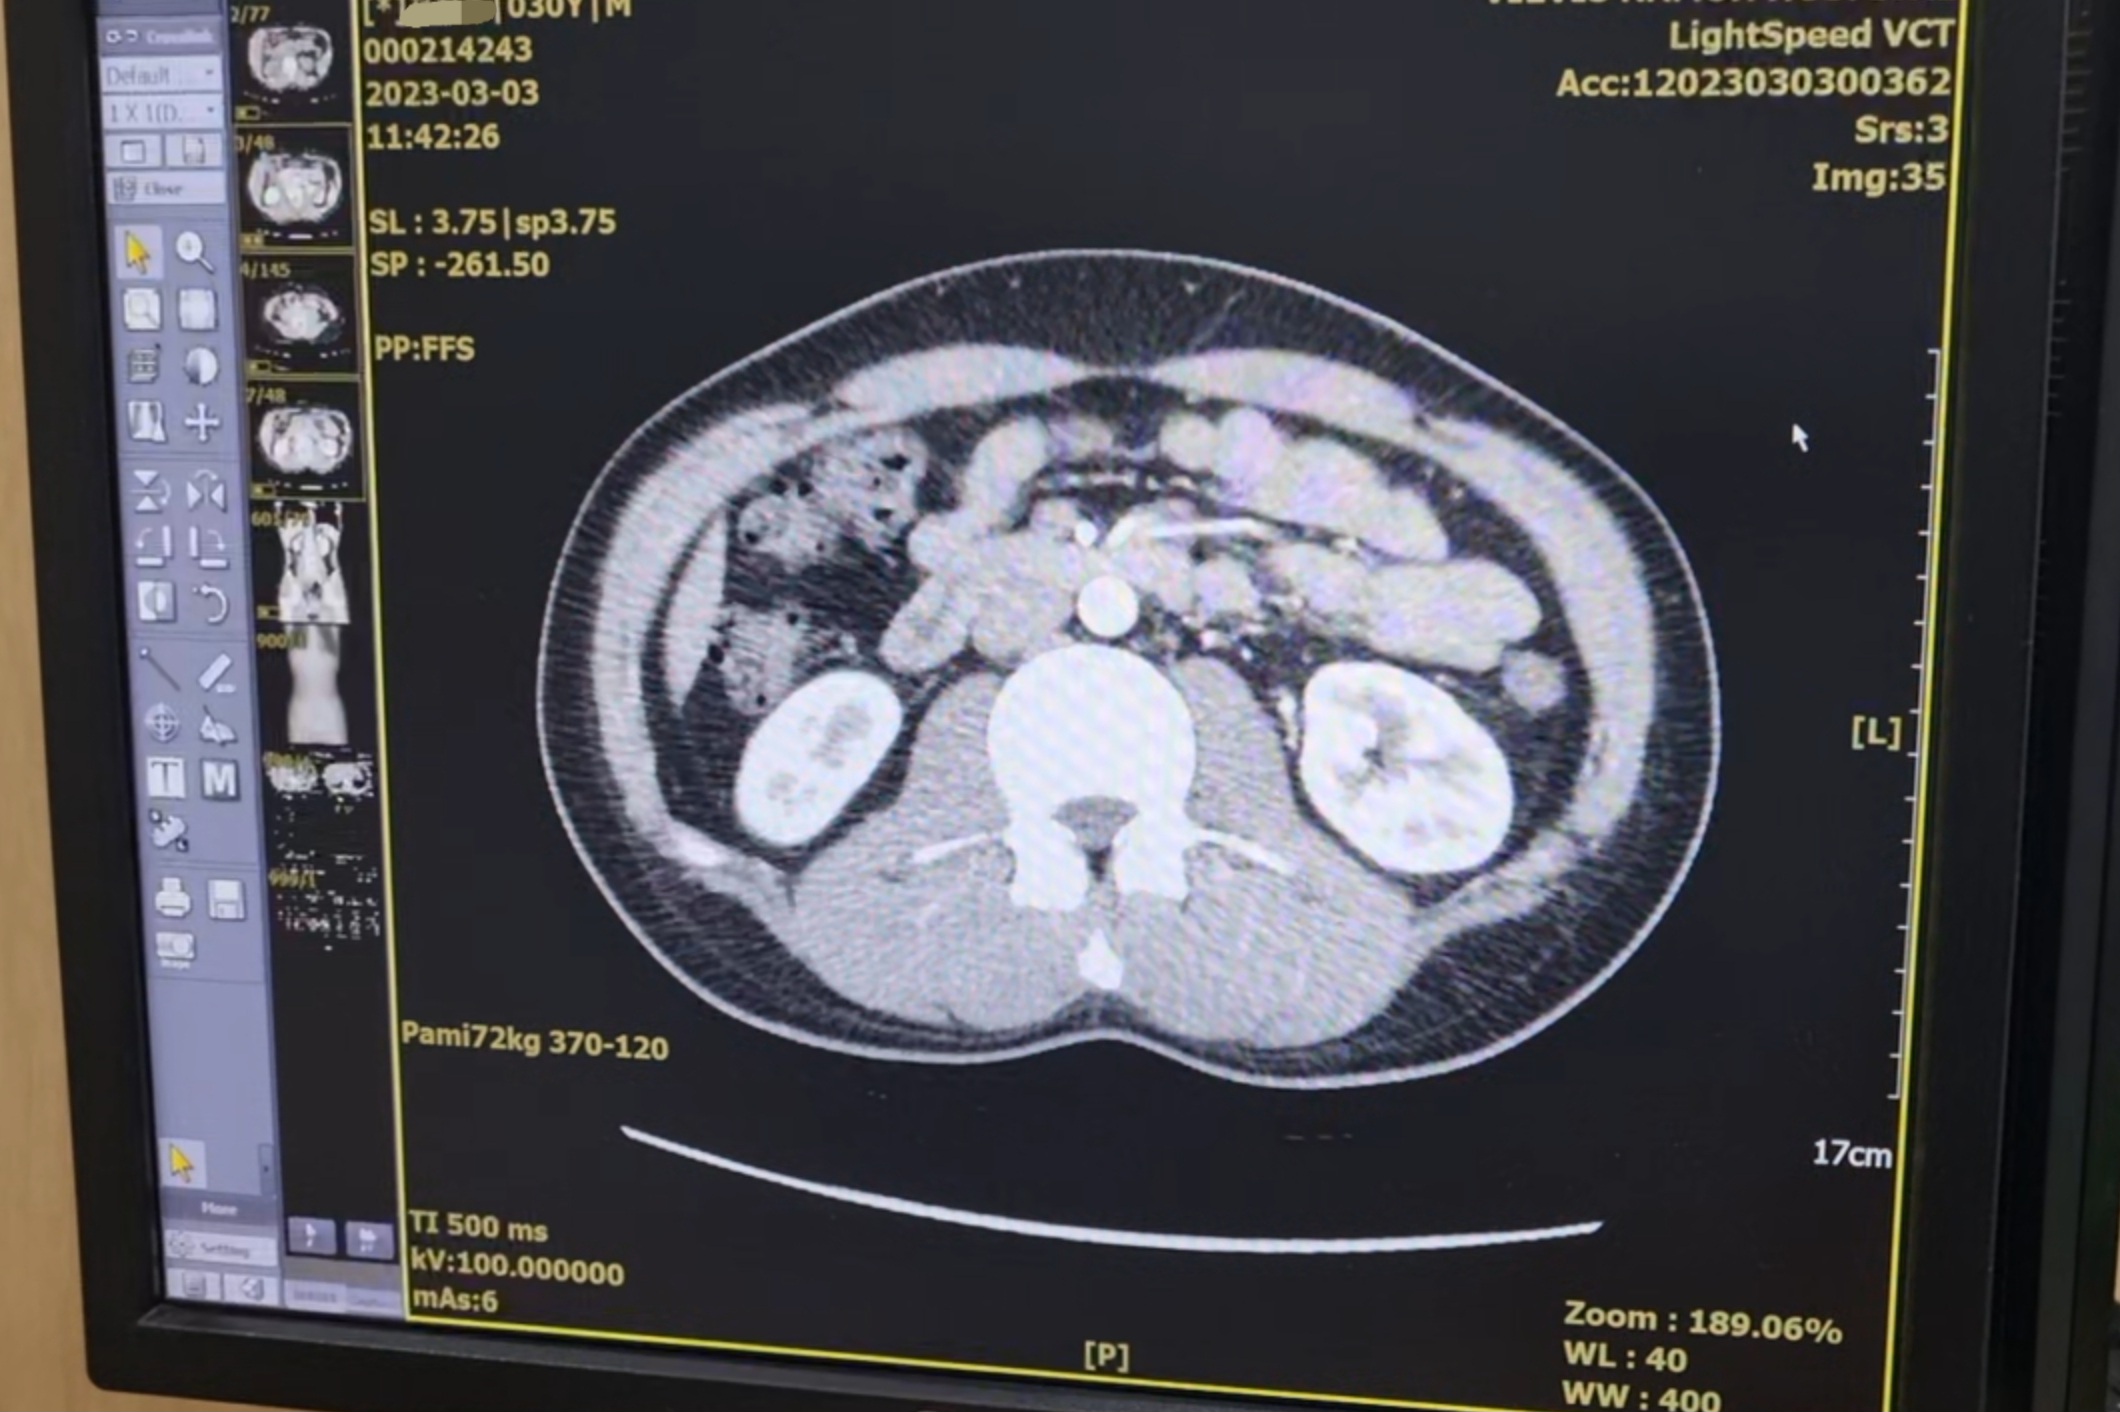

아! CT 찍었는데 한번 봐야겠다!!라고 생각했다

"CT 결과는 어떤가요?"

결과는? 두둥..

no no no no no no... no demonstrable abnormality.!!!

이렇게 강렬하고 직관적인 단어를 내 몸에 적용해 주다니... 평소에 잘 보지도 못하는 단어들인데

선생님도 거들어 주셨다

"아주아주 깨끗합니다 가족 중 암이 있다고 해서 그것도 같이 봤는데 작은 종양 하나 없이 깨끗합니다.

마치 교과서에 나오는 장기를 보는 것 같아요."

한 30초 되는 CT 사진을 동영상처럼 주르륵 넘겨주시면서 설명해 주셨다.

사실 난 이렇게 봐도 어디가 어딘지 뭐가 이상한지 모른다.

그래서 선생님의 해석만을 전적으로 믿는 수밖에 없다.